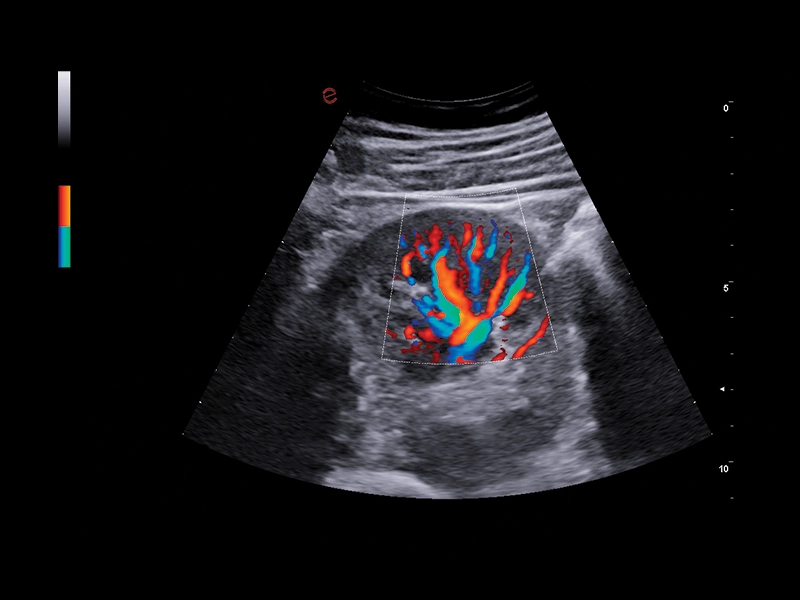

MyLab™E80 - Power Doppler - Gynaecology

MyLab™E80 - Power Doppler - Gynaecology